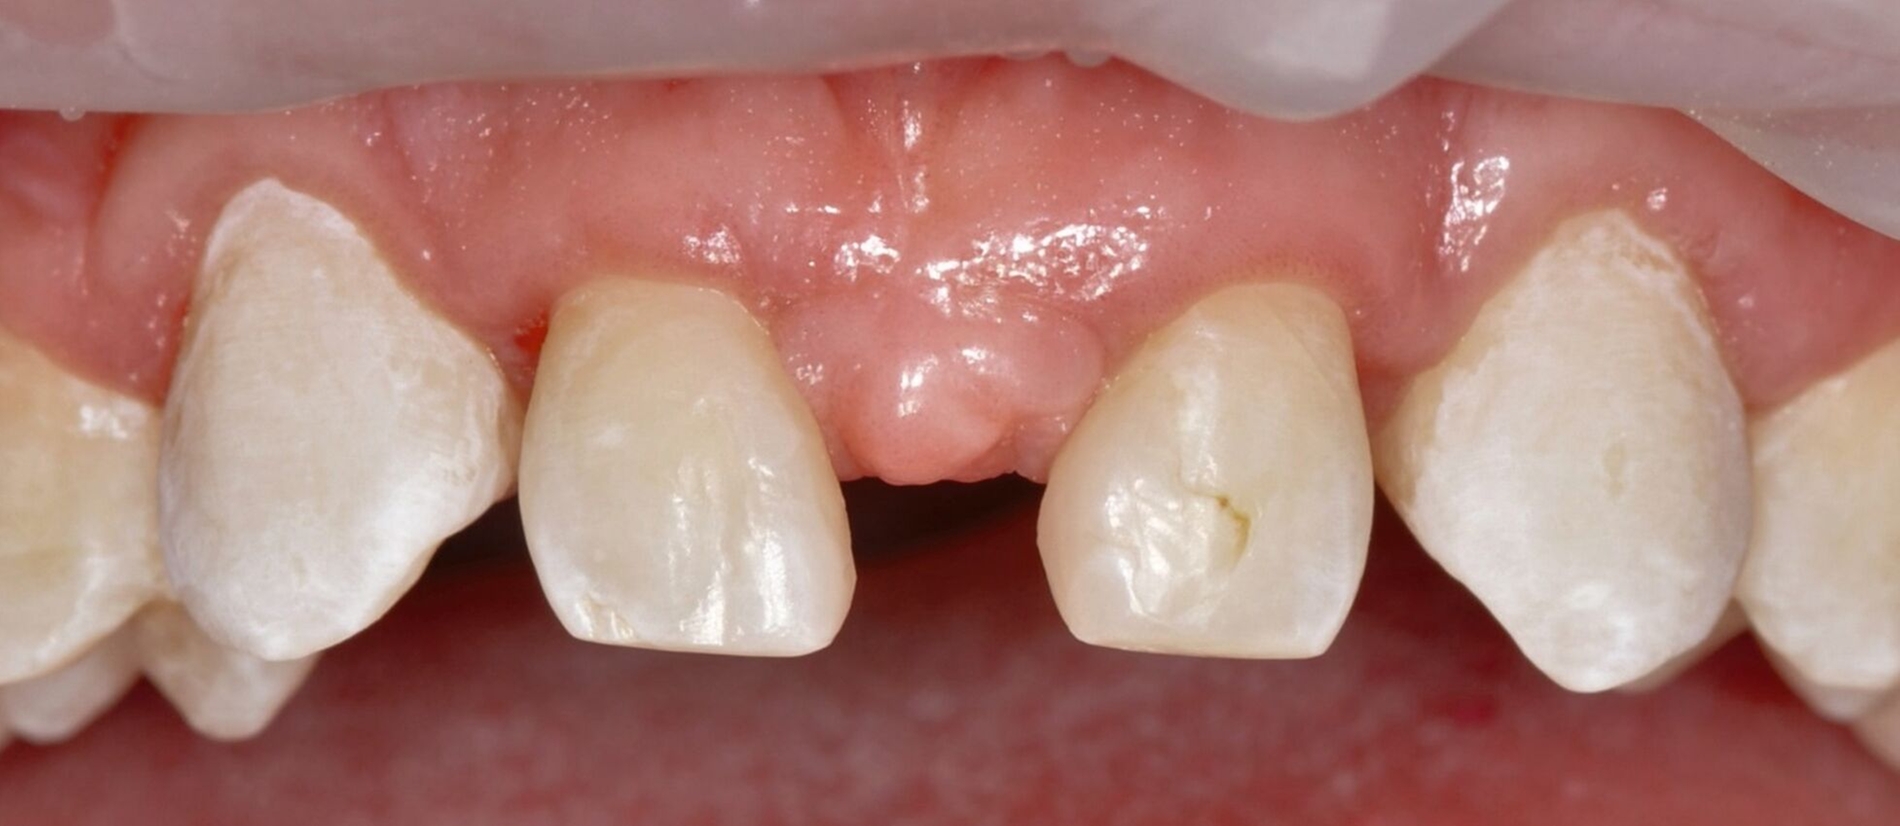

Bei der Erstvorstellung zeigt der Patient ein ausgeprägtes Diastema mediale sowie Restlücken und Asymmetrien im Oberkieferfrontzahnbereich nach kieferorthopädischer Therapie alio loco (Abbildung 1). Aufgrund mangelnder Adhärenz konnten nicht alle kieferorthopädischen Behandlungsziele erreicht werden, was insbesondere aus ästhetischer Sicht Herausforderungen für den restaurativen Lückenschluss mit sich bringt. Erschwerende Faktoren sind die Verschiebung der Mittellinie, die Achsenneigung der Zähne 13, 12, 22 und 23 sowie die inhomogene Lückenverteilung mit ungleich verteilten Lückengrößen (Abbildung 2). Eine erneute kieferorthopädische Korrektur lehnt der Patient allerdings ab. Subjektiv empfindet er insbesondere das kindliche Erscheinungsbild der lückig stehenden, kurz und klein wirkenden seitlichen Schneidezähne als störend. Ziele der Behandlung sind eine präventionsorientierte, ästhetisch-funktionale Rehabilitation des Oberkieferfrontzahnbereichs und eine Harmonisierung des dentofazialen Erscheinungsbildes.

Nach einer präventiven Vorbehandlung in Form einer Professionellen Zahnreinigung und eines individuellen Mundhygienetrainings erfolgt die erste Behandlungssitzung, in der direkte Zahnformkorrekturen mit Komposit (IPS Empress Direct Dentin & Enamel A2, Ivoclar Vivadent, Liechtenstein) in Mehrfarben- und Mehrschichttechnik an den Zähnen 13 und 23 vorgenommen werden. Dabei werden die Eckzähne morphologisch zu seitlichen Schneidezähnen umgestaltet. Zur Orientierung der finalen Inzisalkantenlängen und ‑ausdehnungen dienen palatinal-inzisale Silikonstopps, die auf Basis des diagnostischen Wax-ups gefertigt wurden. Die Approximalflächen werden mithilfe einer individuellen Matrizenverschaltechnik unter Verwendung anatomisch vorgeformter Kunststoffmatrizen gestaltet. An den Zähnen 12 und 22 werden die vorhandenen mesialen Kompositrestaurationen entfernt, bevor Abformungen beider Kiefer mit Alginat erfolgen.

Anschließend werden laborgefertigte Non-prep-Kompositveneers aus dem gleichen Material für die Zähne 12 und 22 hergestellt. Diese werden in einer zweiten Sitzung nach dem Abstrahlen des Zahnschmelzes beziehungsweise der Restaurationsinnenflächen mit Al₂O₃-Pulver und dem Einbringen von Retraktionsfäden adhäsiv (IPS Empress Direct & Flow A2) eingesetzt. Zur Optimierung der Papillenästhetik wird der breite mediale Papillenbereich vor dem Einsetzen der Veneers durch eine externe Gingivektomie reduziert. Der marginale Gingivaverlauf der Zähne 12 und 22 wird unter Berücksichtigung der Lachlinie und in Absprache mit dem Patienten nicht nach apikal auf das Niveau der Eckzähne verlagert. Zusätzlich werden die Zähne 14 und 24 im Bereich der bukkalen Höckerspitzen direkt mit Komposit umgeformt und harmonisch an die neue Frontzahnsituation angepasst.